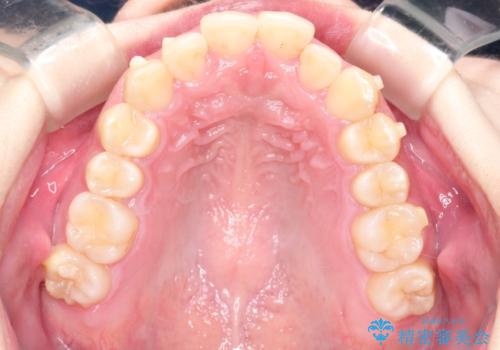

インビザラインでの前歯のガタガタの矯正

- 上下の前歯のがたつきを主訴に来院されました。

歯と歯の間をわずかに削りスペースを作り、インビザラインにて矯正治療を行うこととしました。

使用時間を守っていただけたので、スムーズに矯正を終了することができました。